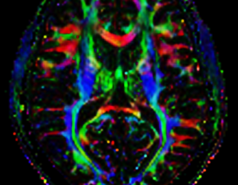

Diffusion Tensor Imaging at 7T